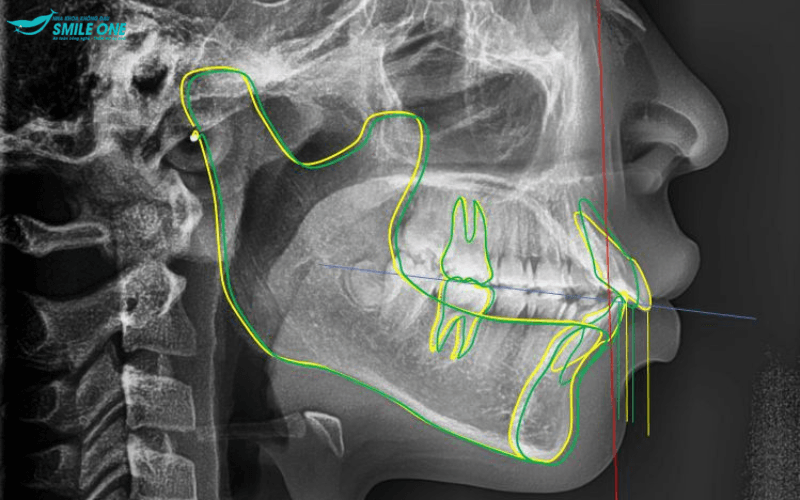

– Chụp X-quang mặt nghiêng: thông qua ảnh phim chụp nghiêng, bác sĩ sẽ phân tích được góc độ của răng, xương và mô mềm, đánh giá được tương quan giữa hàm trên và hàm dưới, giữa răng với hàm và cả mối tương quan với xương sọ.

Với ca niềng răng nào cũng thế, bác sĩ sẽ phải lên phác đồ điều trị cụ thể để tiên lượng được những thay đổi về hàm răng, hướng dịch chuyển của răng sau khi niềng và thời gian niềng dự kiến. Để làm được điều đó, bác sĩ phải hiểu rõ đặc điểm của xương hàm, trục răng, mức độ sai lệch,…của răng.

Những hình ảnh thu được từ phim X-quang kết hợp với hình ảnh thăm khám khoang miệng, lấy mẫu dấu hàm,….bác sĩ sẽ đưa ra được những nhận định chính xác về tình trạng răng của bạn.